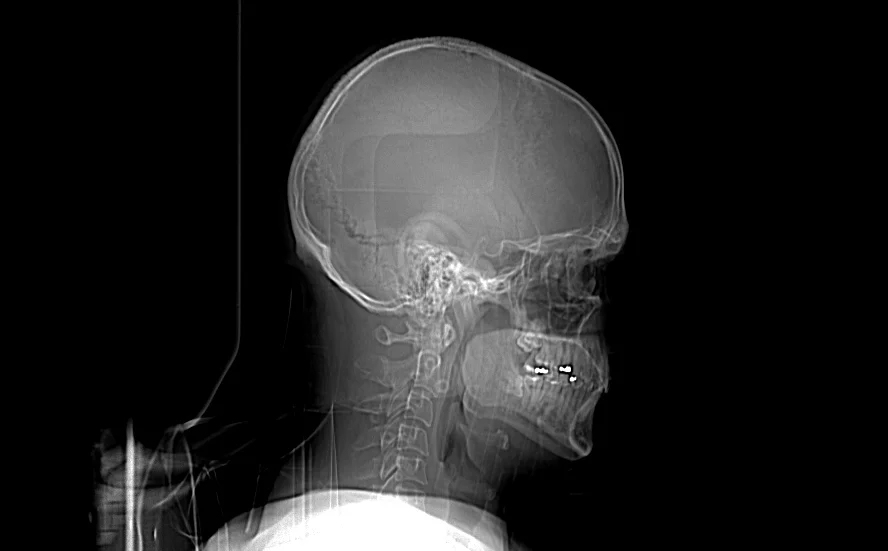

A speeding motorcycle crashed into my rent-a-car in Sorrento, Italy, yesterday. The handlebar hit my ear. Not enough to make it bleed, but it hurt. They put a neck brace on me and carried me on a stretcher into the ambulance. They took X-rays of my head and neck at the hospital and you can see my eyes in this one.